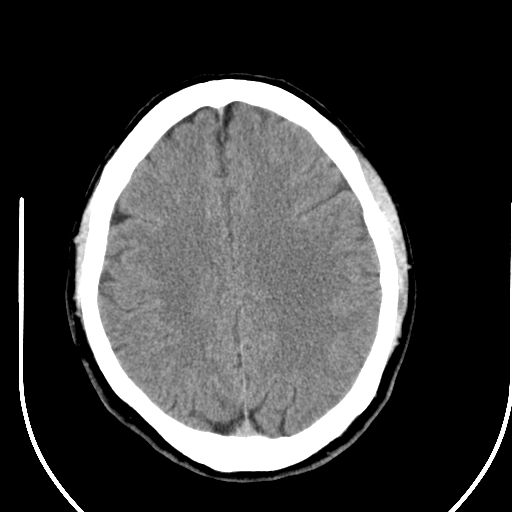

标题: CT25423:头部外伤意外发现右顶叶??? [打印本页]

标题: CT25423:头部外伤意外发现右顶叶???

ct值约13hu。

右顶叶低密度影考虑脑沟

边缘清晰,没有占位效应,不像脑沟,结合ct值,软化灶可能吧

与脑沟没关系,小软化灶或陈旧性感染吧!

看样年纪不小了直接报腔梗,当然你要想报软化灶也是一样的

考虑右侧额叶巨腔隙灶;建议必要时行mri检查。

软化灶。